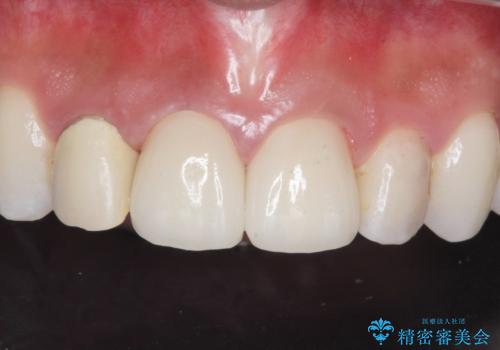

[歯と歯の間の虫歯] ジルコニアクラウン

- メンテナンスの患者様です。レントゲンで歯と歯の間の虫歯が発見されたため治療を行うことになりました。

歯質全体が粗造になっており、インレー治療だと虫歯になる可能性があるので被せ物での治療となりました。

適合が良い被せ物が入りました。

毎日フロスや歯間ブラシを行うことで歯と歯の間が虫歯になるリスクが低くなります。